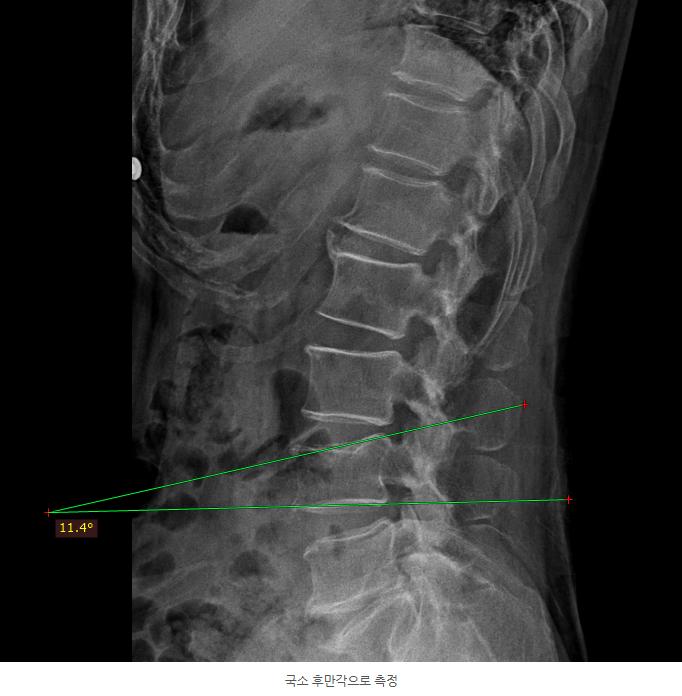

1.png 이미지

위 사진은 T12 흉추 12번 압박 골절이나 압박률이 심하지 않고 신경 증상도 없어

보조기 착용과 약물 및 재활치료 등으로 치료하신 경우

위 사진은 압박골절이 된 추체 자체의 각도 변형을 측정한 것으로 2018년 이전 보험의 경우 적용이 가능합니다.